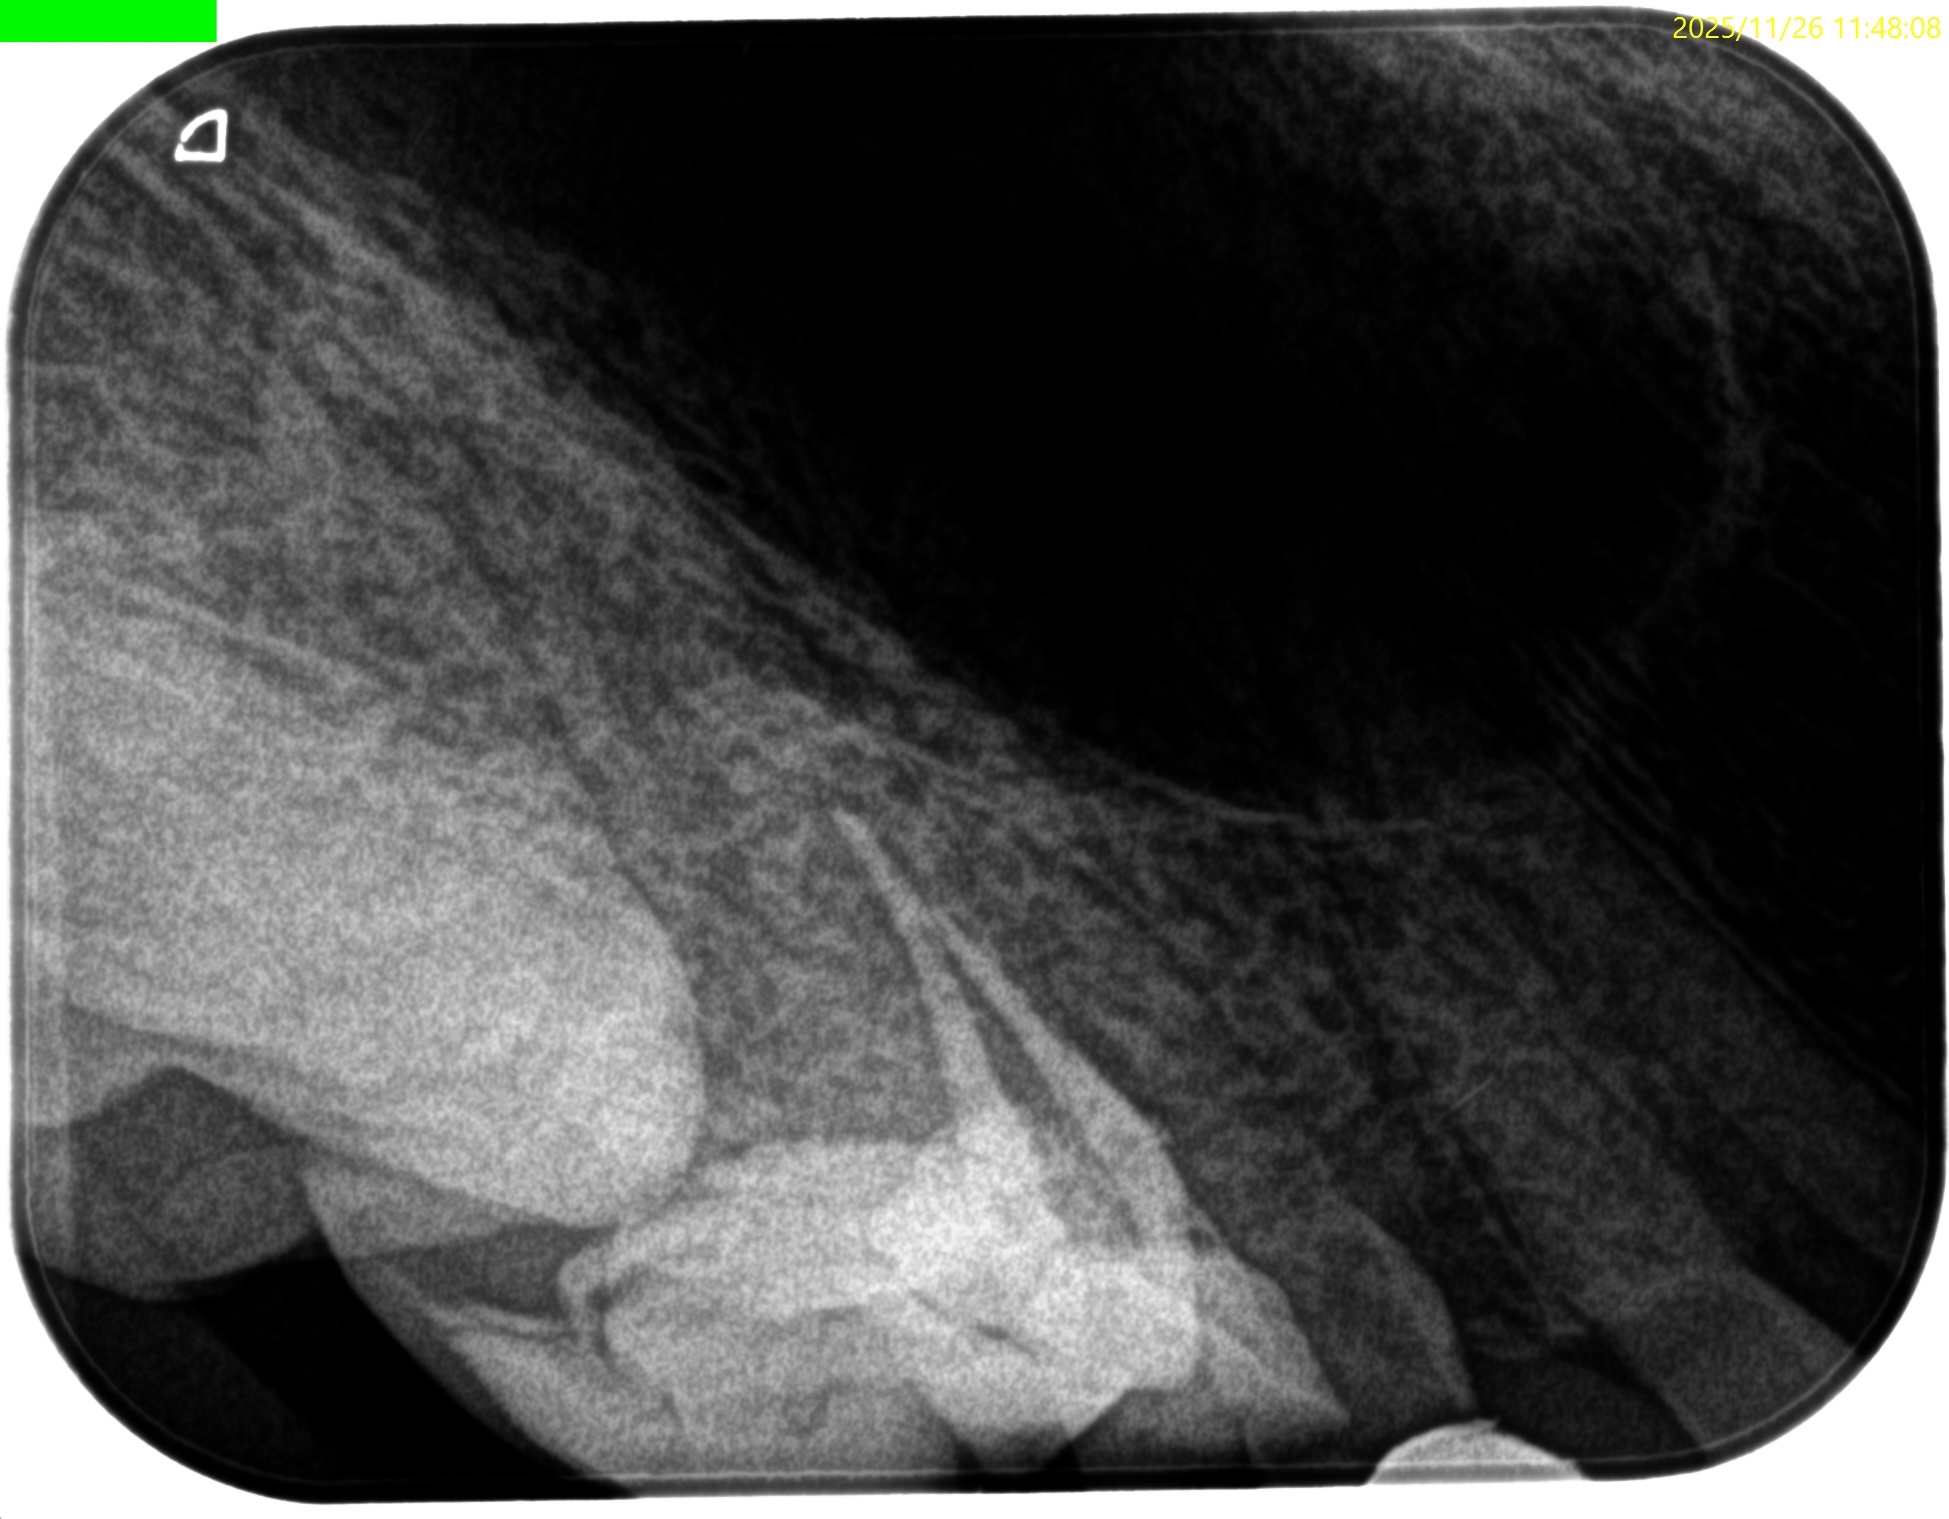

#4 RCT(2025.11.26)

天蓋除去するとBもPも大流血であった。

以下のように作業した。

術後にPA, CBCTを撮影した。

問題はないだろう。

治療は30分で終了した。治療回数も1回だ。